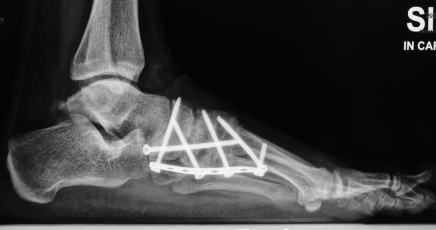

Röntgenbilder

Für die OP-Planung sind auch detaillierte Röntgenbilder unerlässlich. Sie dokumentieren die Fußknochen und den Grad der Fehlstellung aus verschiedenen Blickwinkeln. Am linken Fuß ist die Abweichung des Längsgewölbes und die Verschiebung der Knochen deutlich erkennbar.

Röntgenkontrolle

Die Kontrollaufnahmen unmittelbar nach dem Eingriff zeigen die anatomisch korrigierte Fußform. Die eingebrachten Schrauben stützen den Aufbau so lange bis der Knochen vollständig verheilt ist.